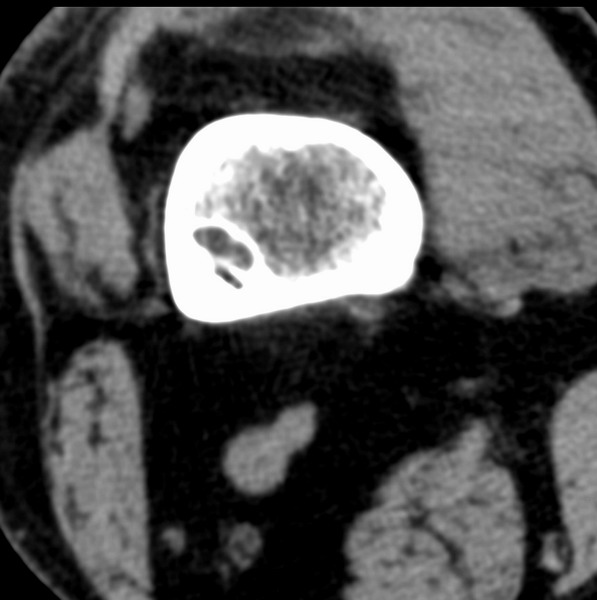

右侧膝关节疼痛一月

男、48

股骨下段、胫骨上段。

1、股骨干骺端病变考虑干骺端纤维性皮质缺损愈后(非骨化性纤维瘤)改变,胫骨近端内生骨瘤(或干骺端纤维性皮质缺损愈后改变);

2、骨关节炎,骨质增生,股骨外侧髁退变性囊肿(关节面软骨下囊肿);

股骨干骺端病变考虑干骺端纤维性皮质缺损愈后(非骨化性纤维瘤)改变,胫骨近端内生骨瘤(或干骺端纤维性皮质缺损愈后改变);

多发内生软骨瘤!

1、股骨干骺端病变考虑干骺端纤维性皮质缺损愈后(非骨化性纤维瘤)改变,胫骨近端内生骨瘤;

股骨干骺端病变考虑非骨化性纤维瘤。

支持非骨化性纤维瘤

非骨化性纤维瘤